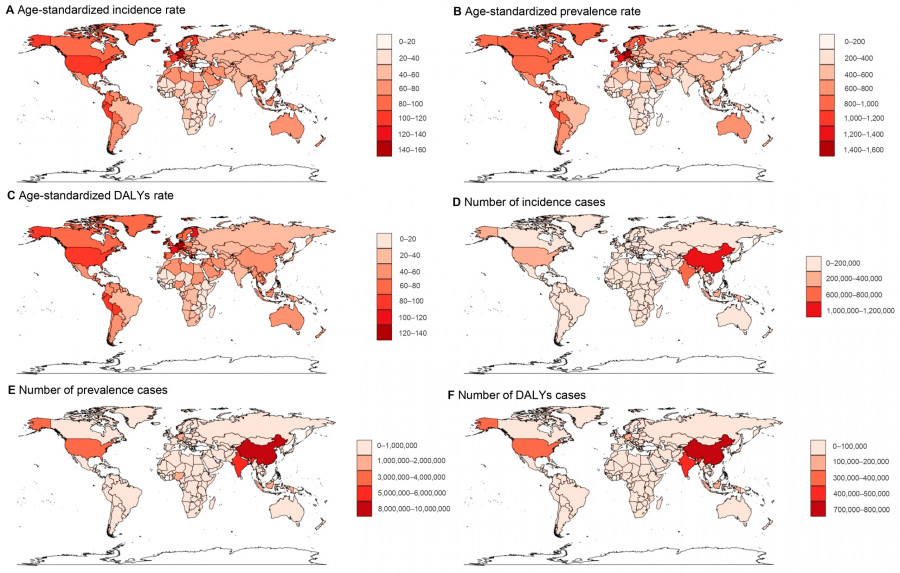

Παγκόσμια κατανομή της ψωρίασης: Τα διαγράμματα απεικονίζουν την ηλικιακά προσαρμοσμένη επίπτωση, τη συχνότητα και την επιβάρυνση της νόσου, καθώς και τον συνολικό αριθμό περιστατικών ανά χώρα. Υψηλότερα ποσοστά παρατηρούνται στη Βόρεια Αμερική και τη Δυτική Ευρώπη, ενώ μεγάλος αριθμός ασθενών καταγράφεται επίσης και σε χώρες με πολύ μεγάλο πληθυσμό, όπως η Κίνα και η Ινδία

Παράλληλα, οι χάρτες της μελέτης δείχνουν ότι χώρες όπως η Κίνα και η Ινδία εμφανίζουν τον μεγαλύτερο απόλυτο αριθμό περιστατικών, όχι επειδή έχουν υψηλότερα ποσοστά, αλλά κυρίως λόγω του τεράστιου πληθυσμού τους. Αυτό εξηγεί γιατί βρίσκονται τόσο ψηλά στη συνολική κατάταξη, παρότι δεν συγκαταλέγονται στις εύπορες χώρες όπου καταγράφονται οι μεγαλύτερες αυξήσεις στα ποσοστά εμφάνισης.